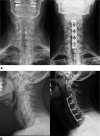

Brachioradial pruritus is a rare condition characterized by chronic localized itching of the dorsolateral upper extremities. Although the exact pathophysiology is still unknown, cervical nerve compression is thought to be a cause. We present the case of a 56-year-old man with a 6-year history of disabling chronic bilateral upper extremity pruritus and pain as well as concurrent neck pain. The patient presented to our office after multiple inconclusive diagnostic evaluations (dermatology, rheumatology, neurology, and psychiatry) and unsatisfactory multimodal conservative treatment attempts. His symptoms markedly impeded his ability to get restful sleep. Imaging of the cervical spine revealed multilevel cervical spondylosis, spinal stenosis with cord compression, and multilevel foraminal stenosis. The patient underwent successful multilevel anterior cervical decompression and fusion and was instantly symptom-free. The present case highlights that patients complaining of itching of the dorsolateral forearms of seemingly unknown etiology should undergo a workup of the cervical spine. If conservative treatment fails, surgical decompression may be considered in select patients.